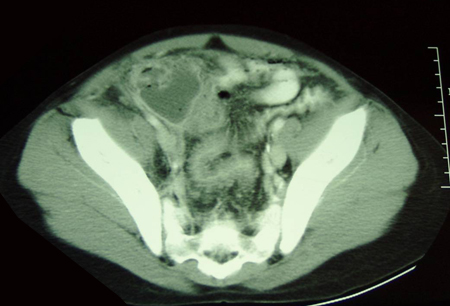

- tomografia computadorizada (TC) de abdome e pelve:

lesão em alvo: massa intraluminal de tecido mole, com uma área de gordura excentricamente posicionada; massa reniforme: alta atenuação periférica e atenuação central mais baixa; massa em forma de salsicha: áreas alternadas de baixa e alta atenuação representando a parede intestinal menos espaçada, gordura mesentérica e/ou fluido e gás intestinal

Mais - tomografia computadorizada abdominal:

mucosa intestinal inflamada e espessada, sinal da impressão digital, dilatação intestinal ou evidência de estenose; mesentério inflamado; abscessos intra-abdominais

Mais - tomografia computadorizada (TC) de abdome e pelve:

lesões descontínuas e segmentares (skip lesions), espessamento da parede intestinal, inflamação adjacente, abscesso, fístulas

intestino delgado dilatado; pode revelar uma zona de transição de obstrução, massa, tumor, abscesso

- tomografia computadorizada abdominal:

obstrução intestinal com padrão de turbilhão do mesentério

distensão gasosa do intestino grosso; pode revelar uma zona de transição de obstrução